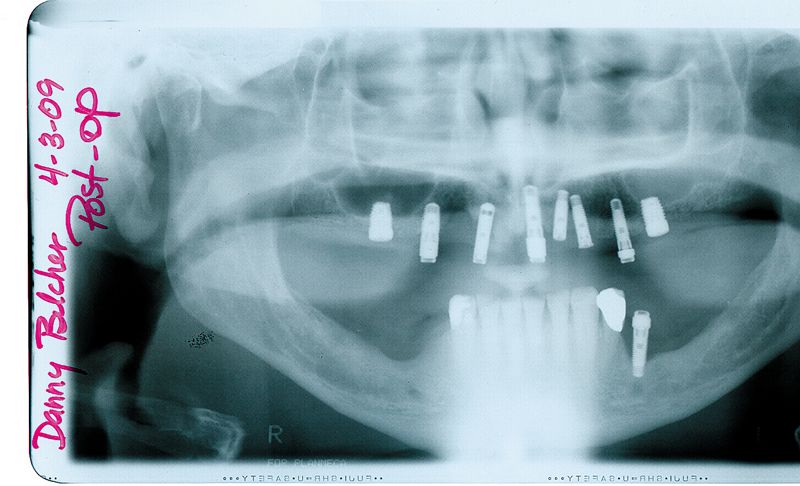

01 A 55-year-old male patient presented with a removable overdenture supported by implants from three different manufacturers (two 6 mm BIOMET 3i Certain® Implants, five Zimmer 4.5 mm Screw-Vents, and one 4.0 mm Calcitek Spline) (Fig. 1). The implants had been placed at different times, by different dentists. The angulations of the implants were severely compromised, with implant thread exposure and soft-tissue recession on several implants (Fig. 2). The patient was known to have a severe gag reflex and was a bruxer with a low lip line. The treatment plan requested by the patient was for a fixed maxillary restoration.

11 The restoration and remaining crowns were returned to the dentist (Fig. 13). The BellaTek Framework was seated intraorally and secured with manufacturer-specific abutment screws. These were tightened to the appropriate torque per each manufacturer’s instructions. The implant-supported crowns corresponding to tooth Nos. 5, 8, and 12 were cemented with NX3 Cement (Kerr) while tooth Nos. 3, 4, 6, 7, 9, 10, 11, 13 and 14 were cemented with temporary cement so the screws could be accessed for removal, if necessary (Fig. 14). A panoramic radiograph was taken (Fig. 15).

Fig. 14?The definitive restoration in place.

Fig. 15?Panoramic radiograph of the definitive restoration.